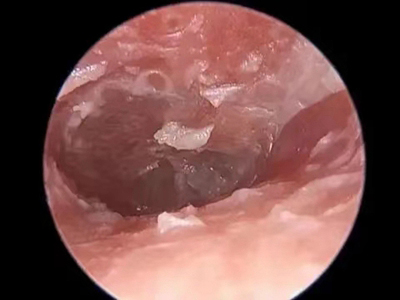

外耳道

肉赘

外耳道炎外耳道有白粉末里边有肉赘图

外耳道炎检查时发现外耳道内有多个白色半透明的肉赘,耳道潮湿,侧壁上还有又细又薄的白色鳞屑,患者表现为持续性疼痛,且逐渐加剧。